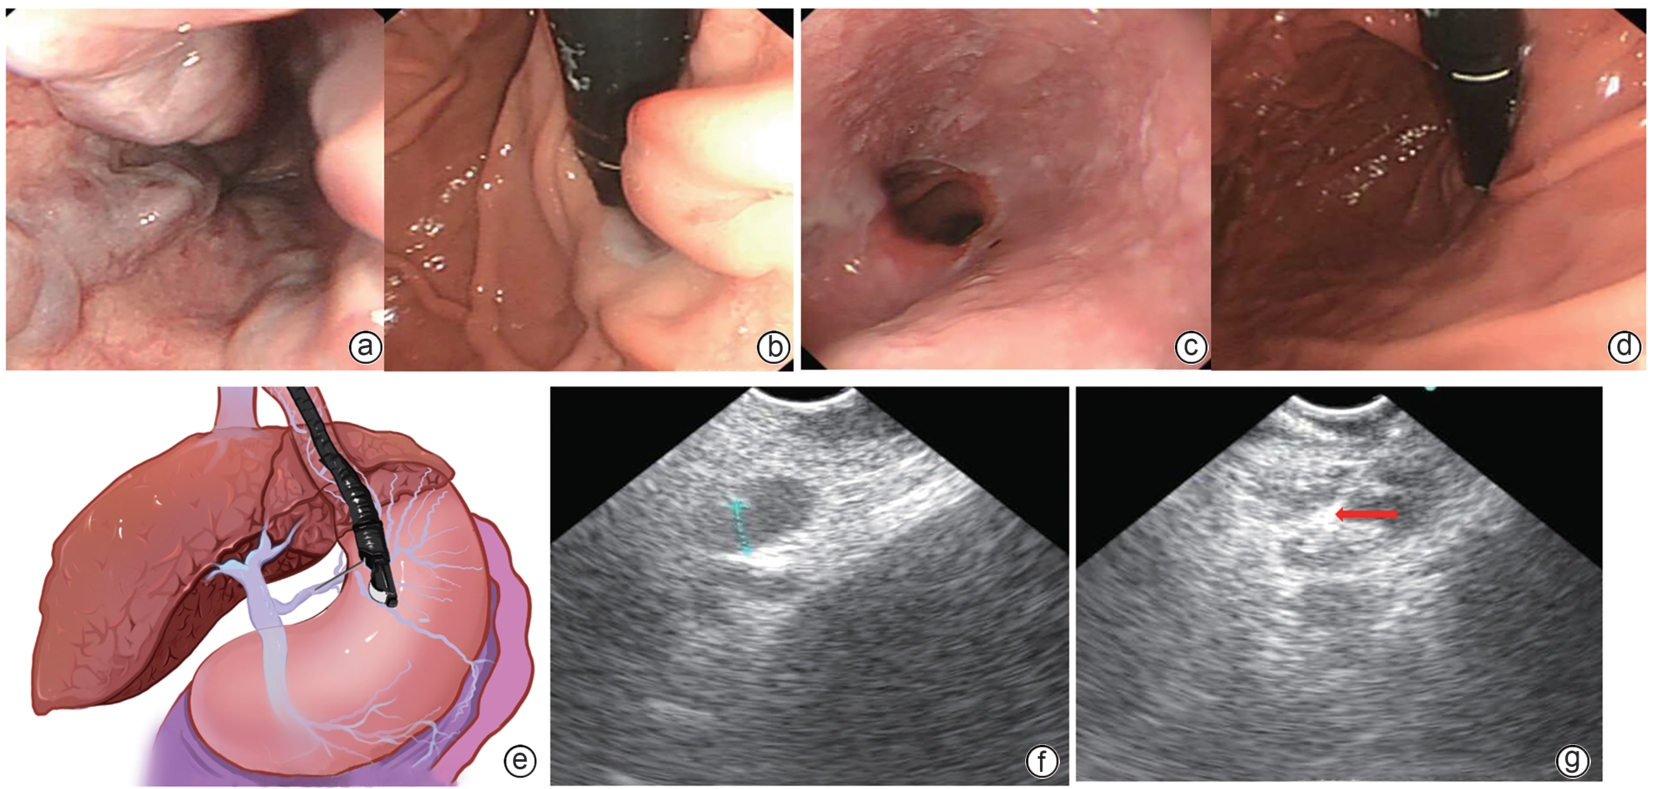

Safety and efficacy of puncture cyanoacrylate selective seal under endoscopic ultrasound versus traditional endoscopy in treatment of gastroesophageal varices: A randomized controlled trial

Jiali MA, Lingling HE, Hongshan WEI, Ping LI, Xiuxia LIANG

2025, 41(6): 1113-1119. DOI: 10.12449/JCH250617

Abstract(1039) HTML (180) PDF (1855KB)(62)

Abstract:

Objective  To investigate the safety and efficacy of puncture cyanoacrylate selective seal (PCSS) under endoscopic ultrasound in the treatment of gastroesophageal varices (GOV).  Methods  A total of 100 patients with liver cirrhosis who underwent endoscopic therapy for the secondary prevention of GOV bleeding in Beijing Ditan Hospital, Capital Medical University, from March 1 to December 31, 2023 were enrolled and randomly divided into PCSS group and traditional endoscopy group. The patients were followed up for 6 months after surgery, and the two groups were compared in terms of clinical outcome and complications. The primary outcome measure was the rate of alleviation or disappearance of GOV, and the secondary outcome measure was variceal rebleeding and death. The independent-samples t test was used for comparison of normally distributed or approximately normally distributed quantitative data between two groups, and the Wilcoxon non-parametric test was used for comparison of non-normally distributed quantitative data between two groups; the chi-square test or the Fisher’s exact test was used for comparison of qualitative data between two groups.  Results  There were 50 patients in the PCSS group, among whom 1 patient was lost to follow-up, and there were 50 patients in the traditional endoscopy group, among whom 3 patients were lost to follow-up. There were no significant differences between the two groups in baseline data such as age, sex, Child-Pugh class, varices grade, and GOV typing (all P>0.05). Compared with the traditional endoscopy group, the PCSS group had significantly better results of the number of endoscopic treatment sessions (t=-15.671, P=0.001), the total amount of tissue adhesive used (t=-2.830, P=0.006), and the rate of alleviation or eradication of varices sclerosis (χ2=7.078, P=0.029). Both groups had low rates of postoperative rebleeding, adverse reactions, and complications, and there were no significant differences between the two groups (all P>0.05).  Conclusion  Compared with traditional endoscopy, PCSS can significantly enhance treatment outcome while maintaining safety standards.